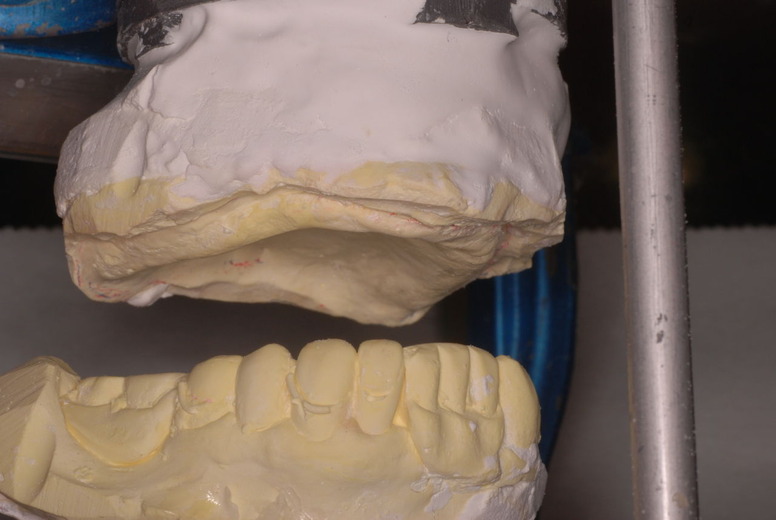

金属にもかかわらず適合が悪い為にプラスチックを重ね着した為に厚くなりしゃべりにくくなっていました。

かなり分厚い入れ歯です。

外注で完成させた入れ歯です。

違いは歯の位置です。あまりに外側で噛むと動くから噛めないのです。